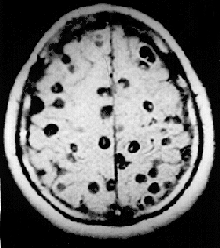

Atteintes cérébrales

L'enkystement dans le cerveau réalise la forme la plus grave appelée neurocysticercose. L'atteinte peut être longtemps silencieuse, passant inaperçue. Quand des troubles se manifestent, les symptômes les plus fréquents sont les crises d’épilepsie survenant dans plus de 52 % des cas reconnus, et les céphalées dans près de 43 % des cas reconnus[1]. La neurocysticercose est l'une des causes les plus fréquentes d´épilepsie acquise. Différents types de crises convulsives ont été décrites : crises généralisées et crises focales, plus rarement myoclonies et aphasie épileptique acquise[20].

Selon sa localisation, le kyste larvaire entraîne les mêmes troubles cliniques qu'une tumeur cérébrale de même localisation[19]. La confusion, les troubles de l'attention aux gens et à leur entourage, les troubles de l'équilibre, peuvent également se manifester. Une localisation dans les ventricules du cerveau entraine leur dilatation (hydrocéphalie) par blocage mécanique.

La cysticercose est difficile à diagnostiquer à sa phase initiale. La neurocysticercose est souvent de découverte fortuite, lorsqu'un scanner, ou une IRM du cerveau, est pratiqué pour une raison quelconque. Il peut s'agir aussi d'une découverte à l'autopsie.

Dans le bilan d'une neurocysticercose, le scanner ou l'IRM sont les examens principaux qui permettent de visualiser les kystes, y compris ceux de petite taille et les cysticerques vivants, en précisant leur nombre, leur taille, leur stade évolutif et les réactions inflammatoires éventuelles[19].